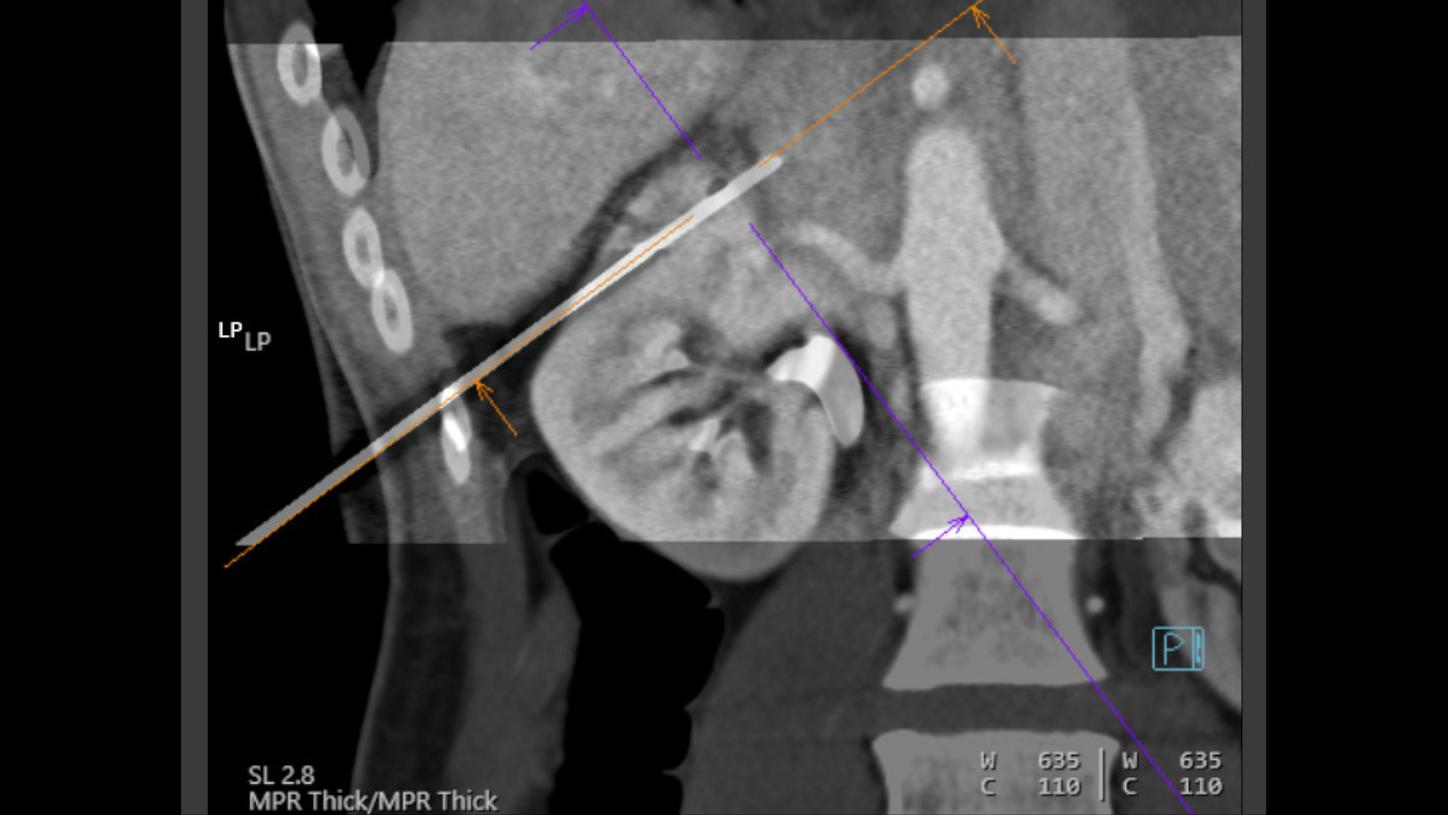

Computed Tomography is moving beyond its traditional diagnostic role to become a key player in early disease detection and therapy planning. This expansion means an even broader patient cohort and resilient productivity demands. You need a reliable partner with products, services, and the infrastructure to support new business models and prioritize environmental sustainability and robustness. Computed Tomography at Siemens Healthineers, with its legacy of listening for almost 50 years, is innovating ahead of these developments, even before potentials become needs.

The NAEOTOM Alpha class